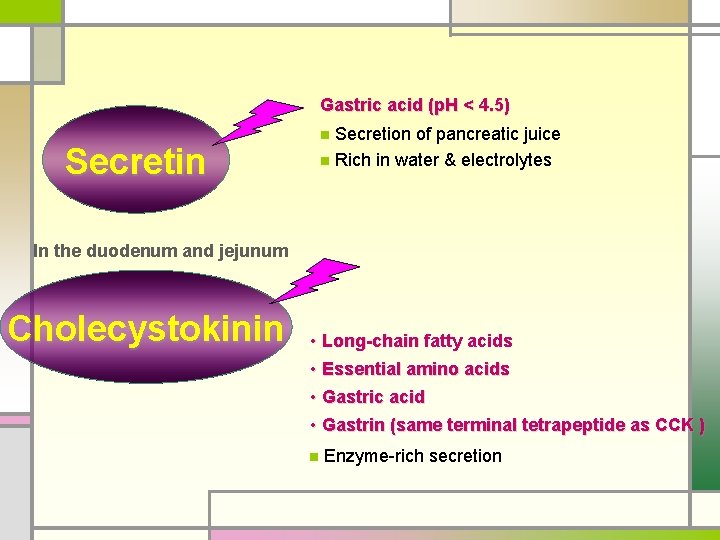

Gastric acid (p. H < 4. 5) Secretion of pancreatic juice n Rich in water & electrolytes n Secretin In the duodenum and jejunum Cholecystokinin • Long-chain fatty acids • Essential amino acids • Gastric acid • Gastrin (same terminal tetrapeptide as CCK ) n Enzyme-rich secretion